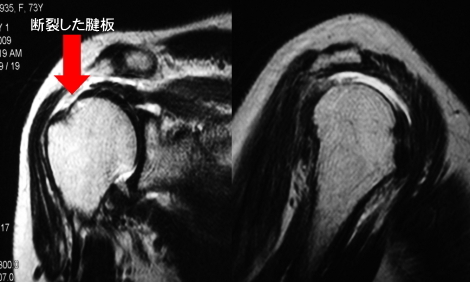

断裂した腱板を関節鏡でみると